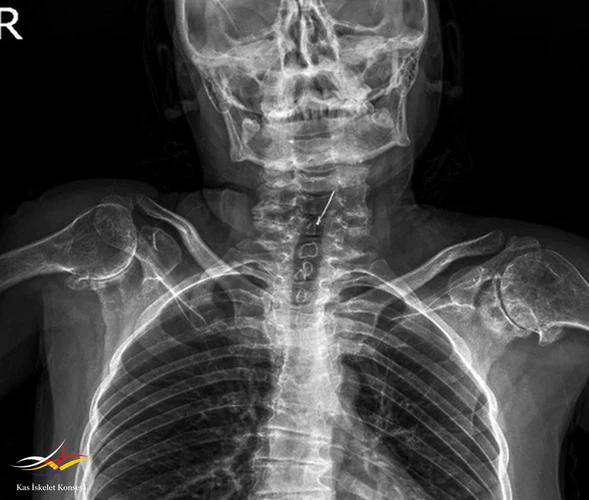

Resim 4.

- Klinik Özellikler: Kısa boy-kısa gövde: Özellikle ergenlik öncesi veya ergenlik döneminde gelişir. Gövde kısalığı ve fıçı göğsü belirgin olabilir. Her iki kol uzunluğu boy uzunluğundan fazla olur

3. Ek bulgular: Omurga büyümesi normal doğumdan sonra başlar, ancak ergenlik öncesinde yavaşlar.

- Spondiloepifizyal displazi tarda (SEDT): Çocukluk sonu veya adölesan dönemde ortaya çıkan, özellikle omurga ve epifizleri etkileyen, genellikle X-bağlı kalıtım gösteren nadir bir iskelet displazisidir.